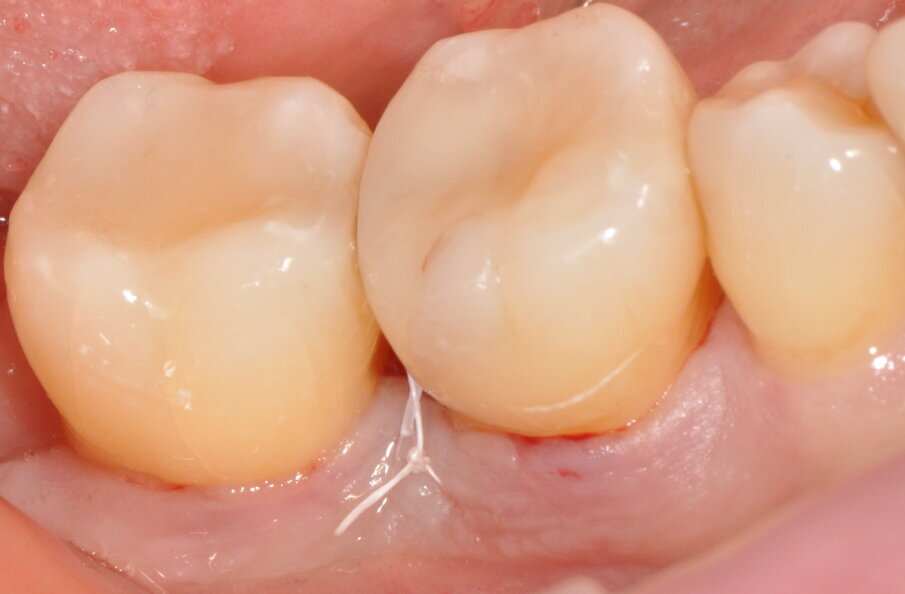

Fig. 13 - Rimozione sutura a 14 giorni.

Fig. 14 - Maturazione dei tessuti e sondaggio a 3 mesi.

La rimozione sutura è eseguita invece a 14 giorni dall’intervento con valutazione della corretta guarigione del sito chirurgico e verifica del rispetto delle norme post-intervento. Nello stesso appuntamento, si consegnano spazzolino manuale post-chirurgico ultra soft (Special Care® TePe®) e scovolino interdentale extra-soft (Extra Soft TePe®) sottodimensionato da utilizzare per le due settimane successive. Il cambio dei presidi domiciliari, con nuova motivazione ed istruzione, viene effettuato ad 1 mese dall’intervento: si consiglia ora di ritornare ad utilizzare lo spazzolino elettrico con testina a setole soft e scovolini interdentali (Original TePe®).

A 3 mesi dell’intervento il sito viene valutato nuovamente attraverso ispezione clinica e indagine radiologica; i tessuti molli risultano sani all’aspetto e al sondaggio (assenza di SOP e BOP, sondaggi MV dell’elemento 4.7 e DV dell’elemento 4.6 rispettivamente di 3 e 4 mm) ed i tessuti duri appaiono re-mineralizzati in radiografia, con il difetto intra-osseo completamente ricostruito. Distalmente all’elemento 4.6 si osservi come la papilla interdentale si sia invaginata durante il periodo intercorso tra la rimozione sutura e il controllo a 3 mesi, ciò è dovuto all’utilizzo da parte della paziente di uno scovolino di dimensioni non adeguate che viene prontamente sostituito. Anche dopo la chirurgia, la paziente rimane un soggetto con Periodontal Risk Assessment alto, a causa della perdita ossea e di elementi dentari rapportata con l’età, pertanto si inserisce in un programma di richiami trimestrali di igiene orale professionale in modo da ridurre al minimo il rischio di recidive.